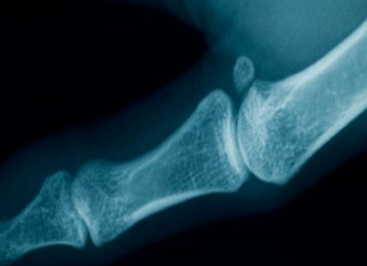

骨密度是衡量骨矿物含量的一个指标。长期缺乏微量元素会导致骨密度下降。钙是骨骼的主要成分。因此,钙缺乏对骨密度有很大的影响,这往往会导致骨质疏松症,影响儿童的健康。婴儿和青少年骨骼生长迅速。如果钙摄入量不足,容易发生骨质疏松症。因此,在这个时候,应该补充钙,并促进钙的吸收与维生素D补充。

对于女孩来说,从儿童到青春期的骨积累和绝经后30年失去的骨相同,所以儿童的骨发育是成人骨的基础。骨质疏松与儿童时期的骨疾病有因果关系。骨质疏松症不仅与未来可能发生的骨质疏松症和脆弱的骨质疏松症有关,而且与儿童时期的骨折现象有着密切的联系。

骨密度仪检测正常值的参考范围在-1到1之间;当T值低于-2.5时,骨质疏松症。骨密度不是越高越好。有些太高也有疾病。两个地方将出现骨密度仪测试的百分比,一个是与峰值相比的百分比,另一个是与同龄人相比的百分比。